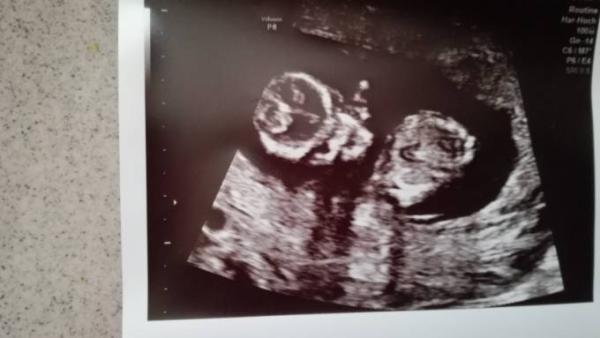

Hallo, hatte das Foto schon mal gepostet aber nur eine Antwort gekriegt... Meint ihr man sieht auf dem Bild schon das Geschlecht??? War 12+5 Eig. lassen wir uns ja überraschn aber bin einfach so neugierig

Bild zu Outing? - Forum für Januar - Mamis